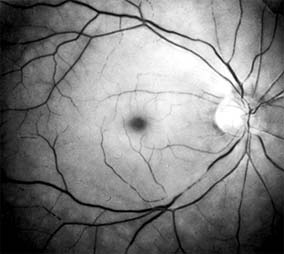

Ophthalmoscopically, the superficial retina becomes opacified except in the foveola, where a cherry-red spot is evident (Figure 10-27). The cherry-red spot is pigment of the choroid and retinal pigment epithelium viewed through the extremely thin overlying foveolar retina and contrasted with the thicker and translucent perifoveolar retina. Twenty-five percent of eyes with central retinal artery occlusion have cilioretinal arteries that spare macular retina and may preserve some central visual acuity. Clinically, the retinal opacification resolves within 4-6 weeks, leaving a pale optic disk as the major ocular finding. In older patients, giant cell arteritis must be excluded and if necessary treated immediately with high doses of systemic corticosteroids. Other causes of central retinal artery occlusion are arteriosclerosis and emboli from carotid or cardiac sources. These are discussed further in Chapter 15.

Figure 10-27

Figure 10-27: Acute central retinal artery occlusion with opaque white retina and attenuated vessels. (Courtesy of University of California, San Francisco.)